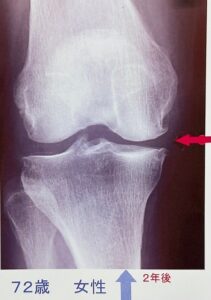

72歳、膝に違和感を感じて来院。

レントゲン きれいです。

早めに受診された方。運動療法で軽快。

次の方 70歳 内側痛

運動療法で軽快された方ですが、

残念ながら軽快すると努力をやめてしまう。

2年後には悪化。